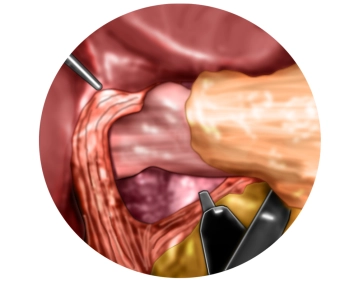

Präparation der Zwerchfellschenkel mit Eingang ins Mediastinum

Präparation des unteren Ösophagus

Toneinstellungen Man geht nun weit ins untere Mediastinum hinein und löst den unteren Ösophagus zirkulär aus seinen Verklebungen heraus. Dabei wird der hintere Vagusnerv eindeutig identifiziert und verbleibt an der Ösophagusmuskulatur. Der Ösophagus wird so weit aus dem Mediastinum heraus gelöst, bis der Bereich des unteren Ösophagussphinkters spannungsfrei im Bauchraum zu liegen kommt.